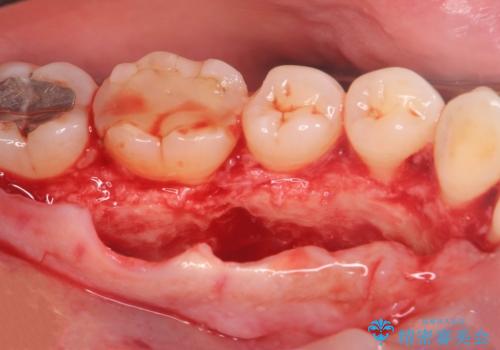

話すのに邪魔な、下顎骨隆起の切除

- 矯正治療を開始するのに伴い、滑舌を含めた改善を計るために、発音の邪魔となる下顎骨隆起の切除を計画します。

手術時間は約30分程度(大きさにより)今回は手術中に、静脈麻酔を行うことで負担なく治療を行う計画としました。

長年気になっていた骨隆起が短時間でなくなり、満足いただくことができました。